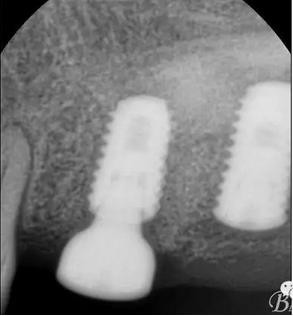

術后x光片,右上6直接上愈合基臺,但未完全就位,右下7手術過程略

這是術后1月的片子,重新就位愈合基臺

戴牙

戴入后口內(nèi)照